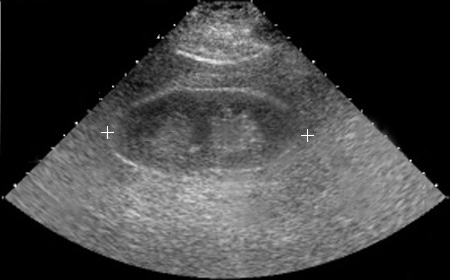

A 52-year-old man has developed polydipsia and polyuria over the past 4 months. On examination he is afebrile with pulse 79/min, respiratory rate 18/min, and blood pressure 160/95 mm Hg. On physical examination his liver span is increased. A chest radiograph shows a slightly enlarged heart with prominent left heart border. Laboratory studies show sodium 140 mmol/L, potassium 4.5 mg/dL, chloride 99 mmol/L, CO2 25 mmol/L, glucose 70 mg/dL, calcium 8.1 mg/dL, phosphorus 4.1 mg/dL, creatinine 3.5 mg/dL, and urea nitrogen 40 mg/dL. A urinalysis shows pH 6.5, sp gr 1.010, and no blood, protein, or glucose. The urine microscopic examination shows many oxalate crystals.

An abdominal CT shows markedly enlarged cystic kidneys bilaterally.